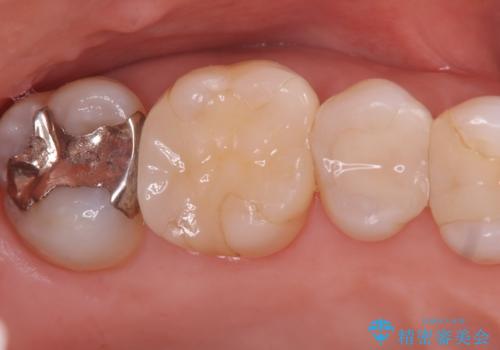

- 昔入れたメタルインレーの下にむし歯が再発したため治療を行った患者様です。

メタルインレーは汚れが付着しやすく、適合も悪いことがあるため、むし歯が再発しやすかったと思われます。

フロスなどの日常の清掃はもちろん不可欠ですが、メタルインレーより汚れが付着しずらいセラミックインレーにて今回は治療を行いました。